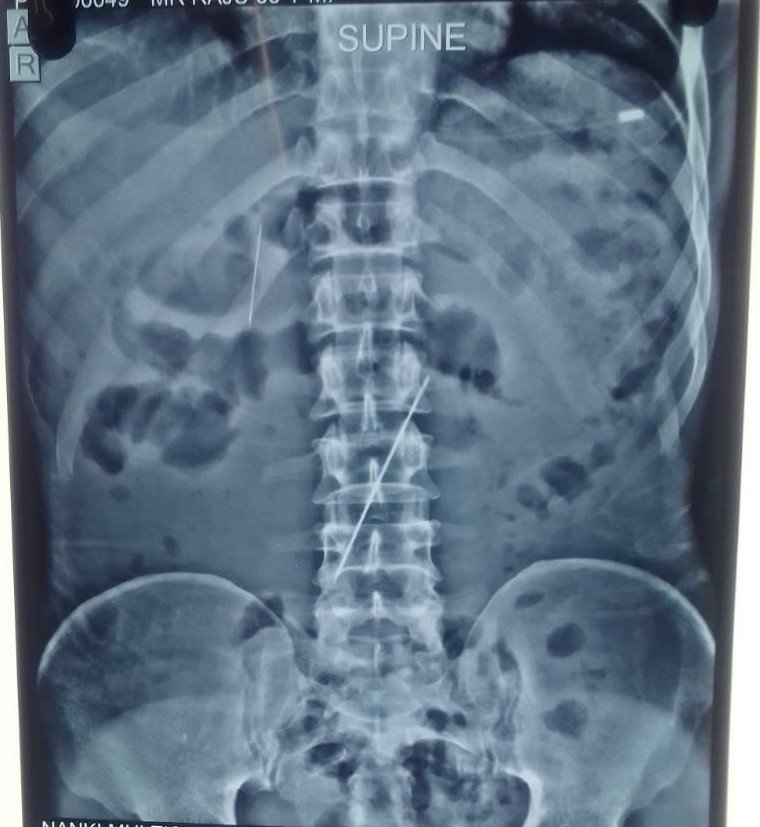

घटना की शुरुआत तब हुई जब राजू ने अपने परिजनों से पेट और सीने में असहनीय दर्द की शिकायत की। दर्द इतना तीव्र था कि उसकी हालत तेजी से बिगड़ने लगी। घबराए परिजन उसे फौरन मुजफ्फरनगर के एक निजी चिकित्सक के पास ले गए। जब सामान्य उपचार से राहत नहीं मिली तो एक्स-रे कराया गया। एक्स-रे की फिल्म ने जो सच उगला उसने वहां मौजूद सभी को सन्न कर दिया। रिपोर्ट में राजू के पेट के भीतर तीन सुइयां स्पष्ट रूप से दिखाई दे रही थीं। मामले की गंभीरता और सर्जरी की जटिलता को देखते हुए, स्थानीय डॉक्टरों ने उसे तत्काल मेरठ मेडिकल कॉलेज (LLRM) रेफर कर दिया।

मेरठ मेडिकल में राजू को सर्जरी विभाग में भर्ती किया गया है। यहाँ वरिष्ठ सर्जन डॉ. गौरव गुप्ता ने कमान संभाली है। डॉ. गुप्ता के अनुसार यह मामला बेहद संवेदनशील है। सुइयां पेट के अंदरूनी हिस्से में कहां अटकी हैं और वे आंतों या अन्य अंगों को कितना छेद चुकी हैं यह अभी पूरी तरह स्पष्ट नहीं है। शरीर के भीतर नुकीली वस्तुओं का होना एक टिक-टिक करते बम’ जैसा है। जरा सी हलचल से आंतरिक रक्तस्राव या अंगों के क्षतिग्रस्त होने का खतरा बना हुआ है। इसलिए मरीज को हाई ऑब्जर्वेशन पर रखा गया है।